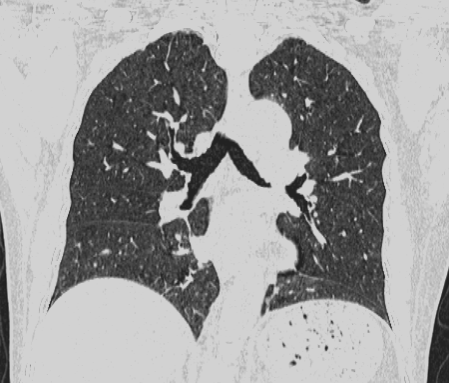

图一:1.2s完成全肺扫描,克服因老年痴呆、精神疾病等造成的屏气问题带来的图像伪影